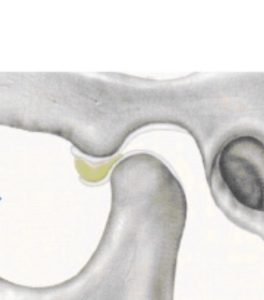

関節円板がさらに強く変形している

口を開けると、下顎頭が変形した関節円板に引っかかる

関節円板の変形が強いので、引っ掛かりが外れない。そのため下顎頭が前に出られず、口が大きく開けられない。